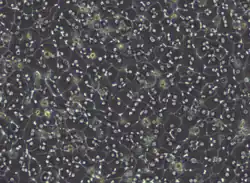

Hepatocytes in cell culture

Hepatocytes in cell culture -